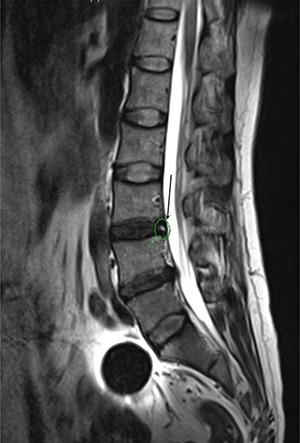

To explore value of different radiographic indexes in the diagnosis of discogenic low back pain (LBP). A total number of 120 cases (60 patients diagnosed with discogenic LBP and 60 healthy people) were retrospectively analysed to identify factors in the diagnosis of discogenic LBP by using univariate and multivariate analyses. A receiver operating characteristic (ROC) curve was drew to show the predictive accuracy of the finally enrolled factors. Among all the included patients, 60 were strictly admitted in the discogenic LBP group while the other 60 were enrolled in the control group. Five results shows significant differences between discogenic LBP and control groups, including Cobb angle, lumbar stability, height of the disc, Modic change and High intense zone (HIZ) based on the results of univariate analysis; lumbar stability, Modic change and HIZ show high value in the diagnosis of lumbar discogenic pain based on the multivariate logistic analysis. The ROC curve shows that good diagnostic accuracy was obtained from the enrolled diagnostic factors including lumbar stability (Angular motion, more than 14.35°), Modic change and HIZ.

探讨不同影像学指标在诊断椎间盘源性下腰痛(LBP)中的价值。回顾性分析120例患者(60例诊断为椎间盘源性LBP的患者和60例健康人),通过单因素和多因素分析确定椎间盘源性LBP诊断中的因素。绘制受试者工作特征(ROC)曲线以显示最终纳入因素的预测准确性。在所有纳入患者中,60例被严格纳入椎间盘源性LBP组,另外60例纳入对照组。单因素分析结果显示,Cobb角、腰椎稳定性、椎间盘高度、Modic改变和高信号区(HIZ)这五项结果在椎间盘源性LBP组和对照组之间存在显著差异;基于多因素逻辑分析,腰椎稳定性、Modic改变和HIZ在腰椎间盘源性疼痛的诊断中显示出较高价值。ROC曲线显示,纳入的诊断因素包括腰椎稳定性(角运动,大于14.35°)、Modic改变和HIZ具有良好的诊断准确性。